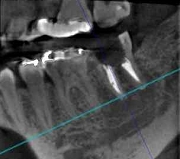

CT画像からは、骨の形や欠損状態がわかるだけでなく、神経の位置や向きなどもしっかり把握できますので、特に、以下のような治療で役立っています。

◆根管治療